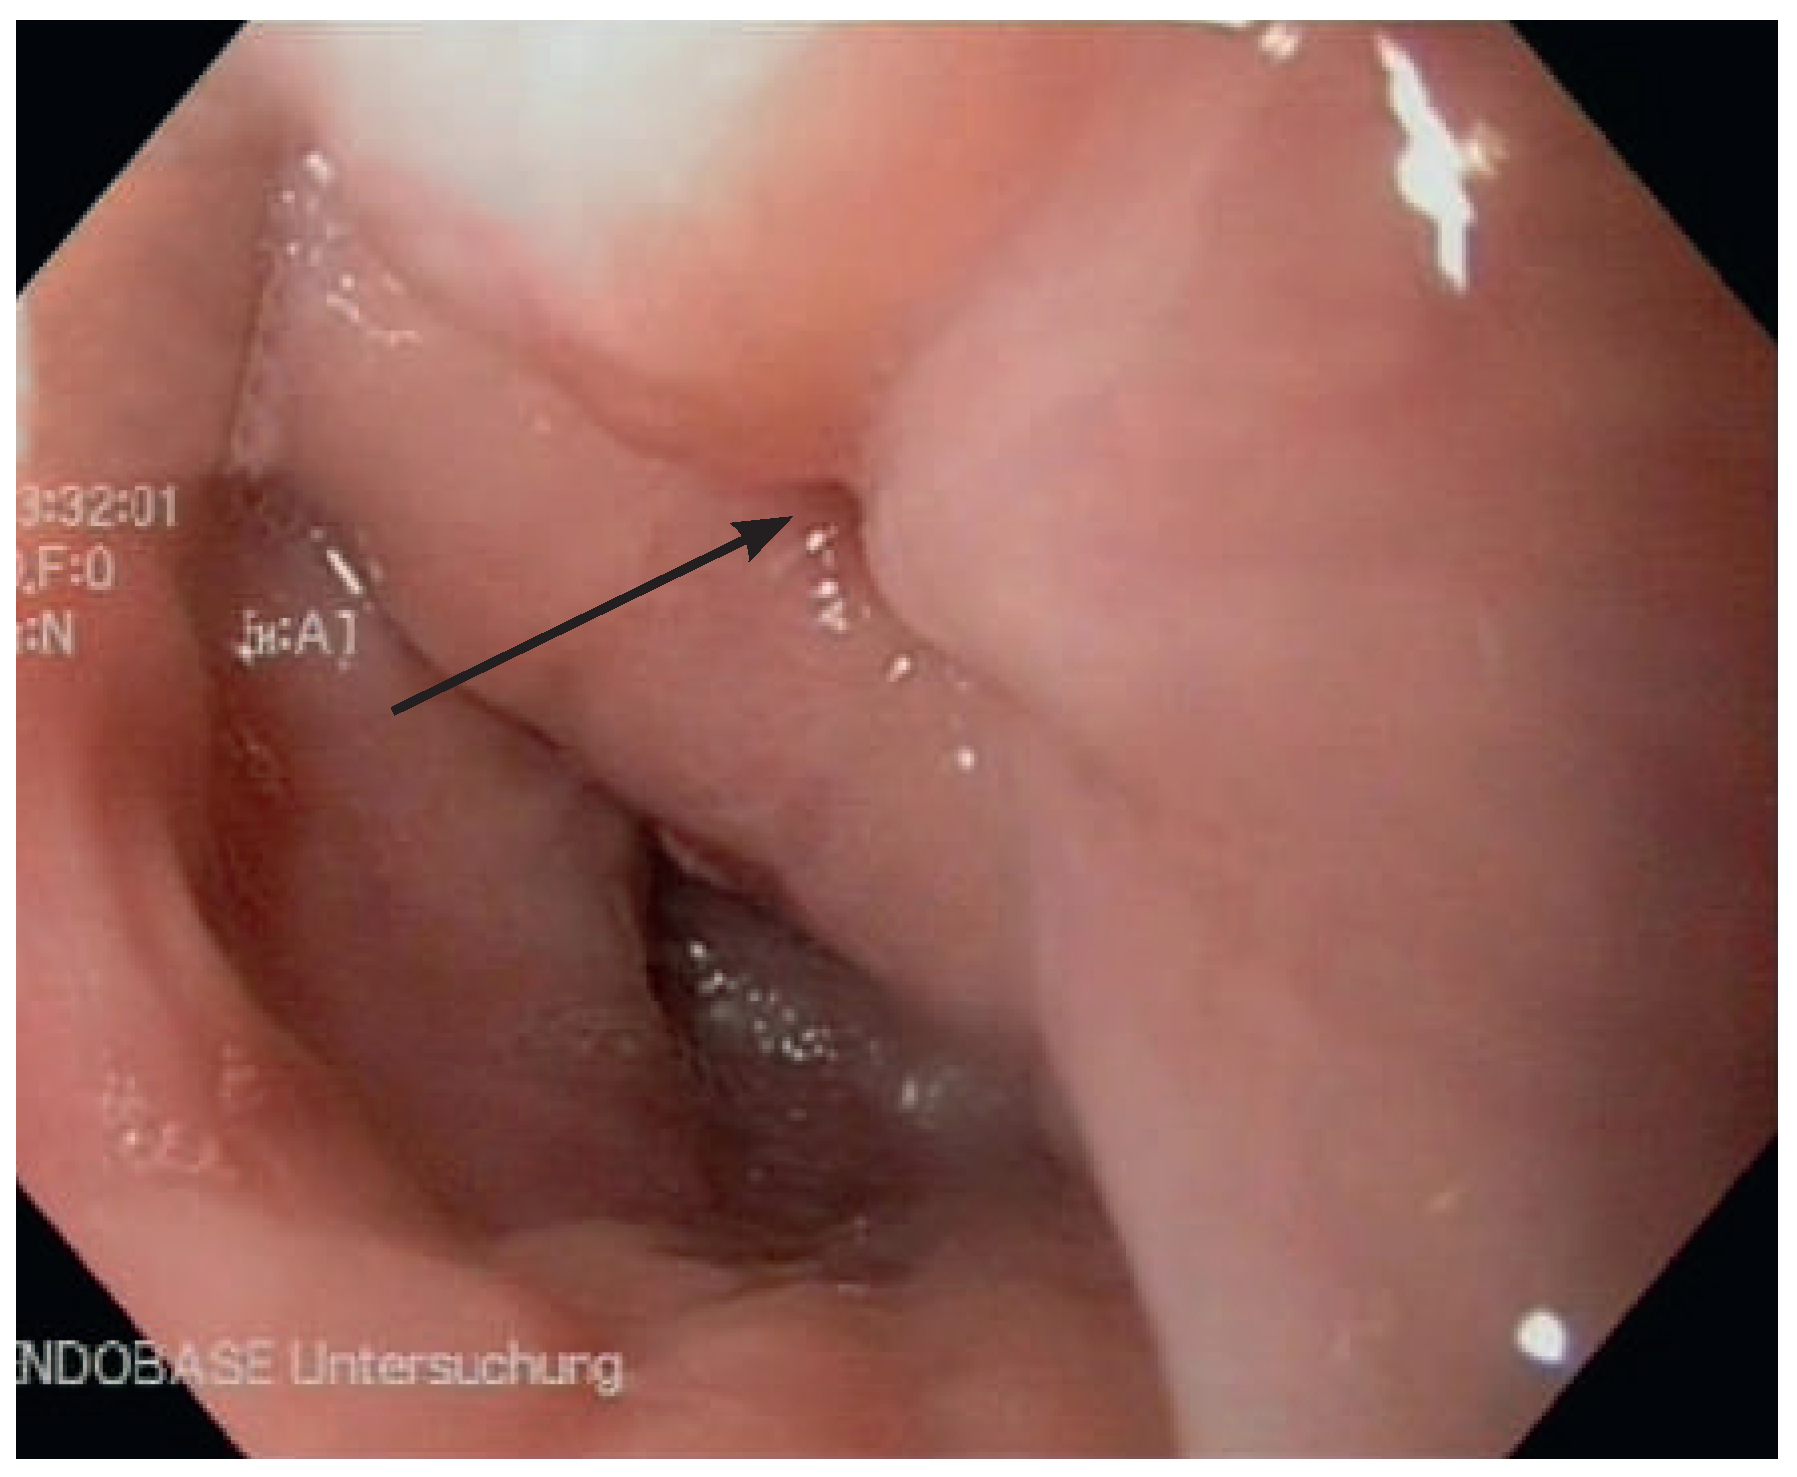

Abbildung 3. Zenker­Divertikel (Abgang des Ösophaguslumens mit Pfeil markiert).

Unter dem Zenker-Divertikel versteht man eine pharyngoösophageale Aussackung der Schleimhaut durch eine Muskellücke unmittelbar über dem oberen Ösophagussphinkter [7]. Diese Entität ist zwar selten, bedeutet aber eine notorische Fallgrube, notabene nicht nur für den Kardiologen, sondern auch für den Gastroenterologen. Das Divertikel liegt ungünstigerweise in der Achse der Intubation, während das wahre Ösophaguslumen komprimiert durch den oberen Sphinkter exzentrisch abgeht (Abb. 3). Eine Intubation des Ösophagus ist nur unter Sicht möglich und erfordert selbst dann noch besondere Sorgfalt und Geschick. Auch nach Divertikel-Operation verbleibt manchmal ein asymptomatisches Residuum, so dass auch bei behandeltem Zenker-Divertikel grosse Vorsicht geboten ist.